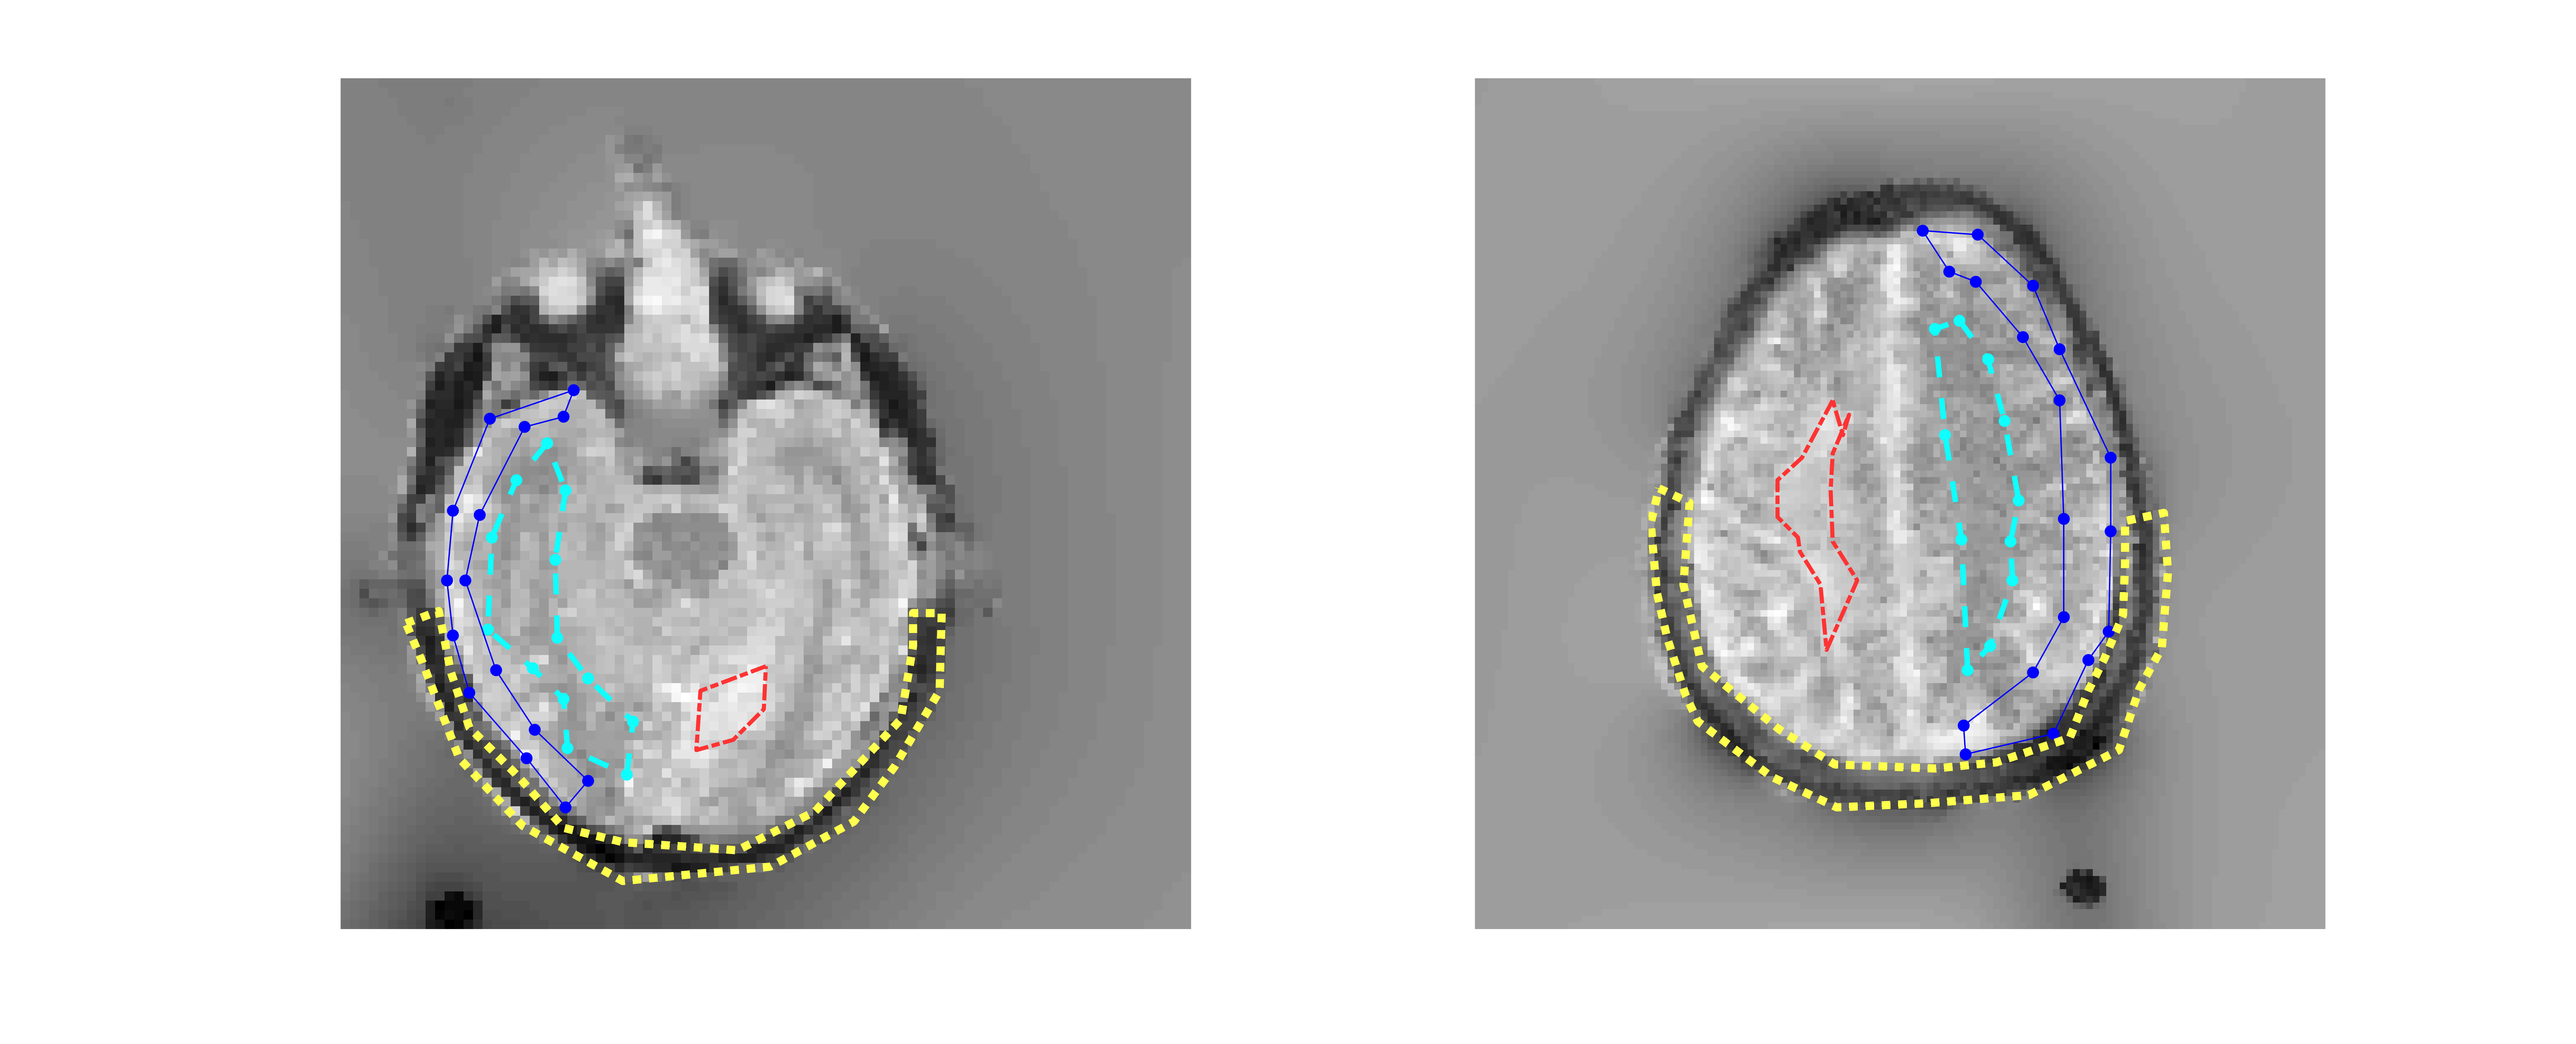

To evaluate the proposed model-based reconstruction approach numerical FFC imaging data were simulated using parameters measured from FFC imaging scans of brain stroke patients at the University of Aberdeen as part of a separate study (PUFFINS study, see details in section 3.2). The numerical phantom followed a schematic geometry and dispersive characteristics of an axial head scan with four regions (see Figure 3), representing the subcutaneous fat (region of interest (ROI) 1), the tissues surrounding the brain (ROI 2), the brain (ROI 3) and a stroke-like lesion (ROI 4). T1subscript𝑇1T_{1} values were simulated by means of a power-law dispersion with model parameters a𝑎a and b𝑏b, 1/T1=a(B0E)b1subscript𝑇1𝑎superscriptsubscriptsuperscript𝐵𝐸0𝑏1/T_{1}=a({B^{E}_{0}})^{b}, coarsely in line with proton T1subscript𝑇1T_{1}-NMRD profiles of fat (ROI 1), white (ROI 2) and grey matter (ROI 3) and stroke lesions (ROI 4) measured in vivo from the PUFFINS patients cohort (data to be published). The values retained for the different evolution fields and times are summarized in Table 1 and Table 2, respectively, and served as a ground truth for the validation of the T1subscript𝑇1T_{1} quantification. The numerical FFC imaging phantom was first generated as a vector graphic to be subsequently converted to matrix data to allow for any desired sampling resolution. In this case we used an image resolution with matrix size of 128×128128128128\times 128 pixel, which is typical for the original FFC imaging of stroke patients. Tissue reference values were assigned for each ROI and a data series was generated using the signal equation in 3. Additionally, a small constant phase offset was introduced for each α𝛼\alpha.

The simulated high noise level can be seen as residual noise in the reconstructed T1subscript𝑇1T_{1} maps of the pixel-wise fitting approaches (Figure 3). Simultaneously, a difference to the simulated reference is visually noticeable in the pixel-wise fitting approach. The H1 approach is able to reduce these outliers but suffers from blurring at image edges. The proposed model-based method is able to reduce outliers throughout all noise levels and is visually closer to the simulated reference values. Plots of C𝐶C and 𝜶𝜶\bm{\alpha} in Supporting Information Figures 1-1 show similar results. The single-field pixel-wise fitting approach even fails to capture the correct phase of the simulated phantom. A pixel-wise relative absolute difference plot (Figure 4) confirms this visual impression of reduced noise using the proposed approach. The proposed method shows an up to 18 fold lower mean error in the phantom, computed over all pixels, than standard pixel-wise fitting. The error increases with increased noise level, as can be expected. Difference plots also reveal a slight bias of the proposed method. The bias of the methods is further assessed in 2D joint histogram plots (Figure 5). For these plots, T1subscript𝑇1T_{1} values of all fields are combined to form a single plot. The proposed method shows slight underestimation of high T1subscript𝑇1T_{1} values, as reflected by points lying below the identity line. However, noise could be greatly reduced compared to the pixel-wise fitting and different T1subscript𝑇1T_{1} ranges are clearly separated and show a similar distribution as the simulated values. Fitting with the standard method took approximately 100 seconds. The proposed method took roughly 120 seconds.

Figure 3: Multi-field T1subscript𝑇1T_{1} maps obtained from simulated FFC imaging inversion recovery data. The reference T1subscript𝑇1T_{1} maps for three different evolution fields (200 mT, 21.1 mT and 2.2 mT) are shown at the top. The different reconstruction methods are presented in each row. Standard refers to single field pixel-wise fitting, multi-field to combined field, pixel-wise fitting approach and H1 to the model-based approach with regularization using the squared L2superscript𝐿2L^{2}-norm of the gradient. The proposed method is shown in the last row. The columns show increasing noise from left to right.